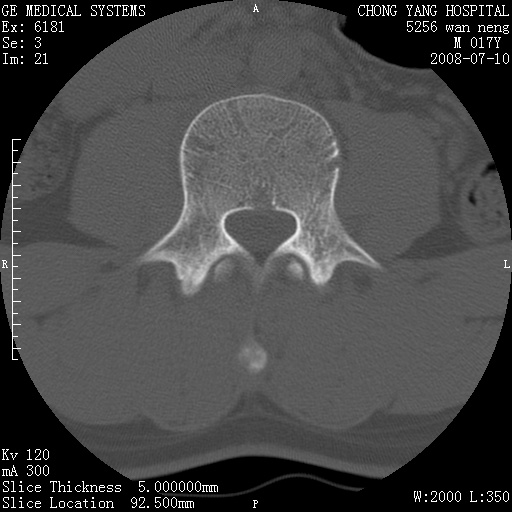

腰3、4椎弓崩裂

腰3、4椎弓不连

支持:腰3、4椎弓峡部崩裂。

腰3、4椎弓峡部不连

支持:腰3、4椎弓峡部崩解。

腰3、4,如受过外伤则为陈旧骨折,否则为骨质不连

图片漂亮,目前也只能看到腰3、4骨质不连

腰3、4椎弓峡部裂。

腰3、4椎弓峡部裂。支持

重建图像见多个椎弓峡部不连(不足为据),平扫未见异常。

支持腰3、4椎弓峡部崩裂。